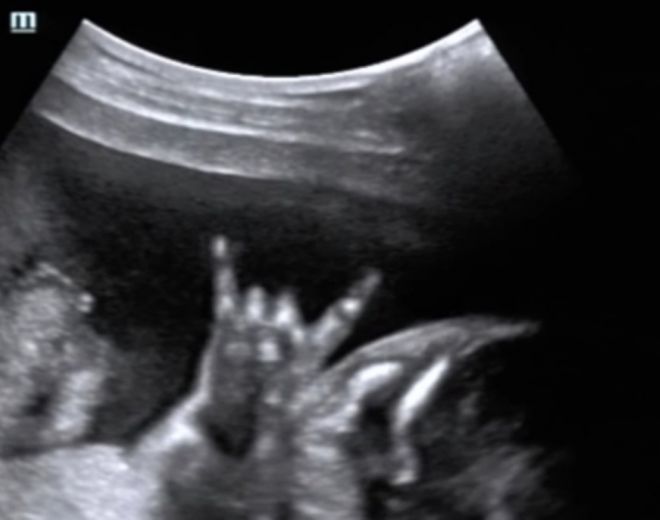

Բնավորությունը առաջ է գալիս մանկուց։